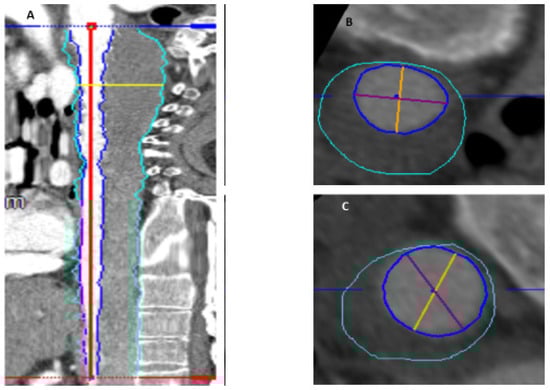

Thrombus volume calculations of the aortic segment from the left subclavian artery until the celiac trunk were performed on preoperative and postoperative computer tomography angiography (CTA) scans. Three-dimensional CTA reconstruction was performed by means of a dedicated software (Aquarius iNtuition, TeraRecon, Foster City, CA, USA); the step-by step thrombus volume measurement technique was previously described [14]. Volume rendering and measurements were performed by two experienced vascular surgeons in order to reduce bias. Using multiplanar planar reconstruction (MPR) and curved planar reconstruction tools, the aortic lumen and thrombus volume were visualized in the venous phase. After generation of the centerline, the thrombus areas were multiplanarily contoured and displayed in straight MPR reconstruction, and the marked areas were checked and manually corrected whenever necessary. In the preoperative CTA after contouring and selection, the chronic mural thrombus was quantified using the volume calculator function. Slices of the postoperative CTA were analogously reconstructed and marked, and the new-onset thrombus volume was calculated as the difference between the postoperative total thrombus volume and the volume obtained in the preoperative CTA (Figure 1).

Figure 1. Thrombus volume measurements before and after the FET/CET procedure using a dedicated software. (A) Centerline in the true lumen, thrombus area has been marked and measured manually for each CT slice (grey area), separated from the true lumen. (B,C) Volume of the thrombus was measured by subtracting the true lumen from total aortic diameter.